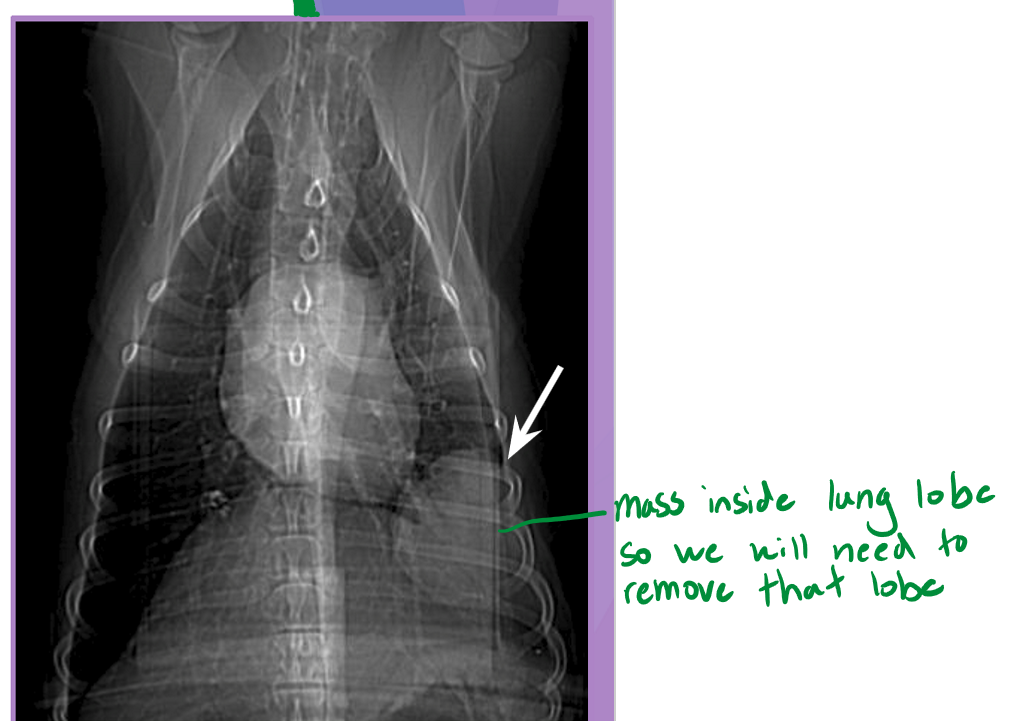

Lung lobectomy

Normal lung volume

right lung - 58%

left lung - 42%

lobectomy: partial or complete removal of a lung

dogs easily tolerate up to 58% removal

indications

partial lobectomy

focal lesion at peripheral ½ to 2/3 of lung lobe

neoplasia

granuloma

bulla

biopsy

complete lobectomy

large amount of purulent material (abscess)

trauma

lung love torsion

large / multifocal lesion

intercostal thoracotomy or median sternotomy

remove lung at pedicle

ligate main artery, bronchus, vein

all the way to hiatus